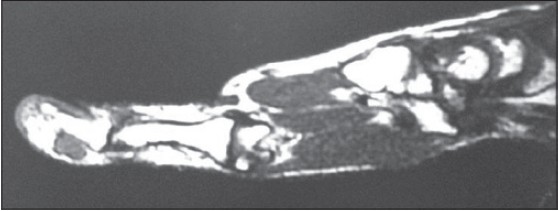

Plain X-ray of hand was normal [Figure 1]. Magnetic resonance imaging (MRI) was suggestive of swelling arising from insertion of flexure pollicis longus tendon, dark on T1 and bright MRI appearance on T2-weighted image [Figure 2] and [Figure 3]. They gave differential diagnosis of synovial swelling and glomus tumour. | Figure 2: T2 weighted Magnetic resonance imaging showing swelling arising from tendon insertion

Click here to view |